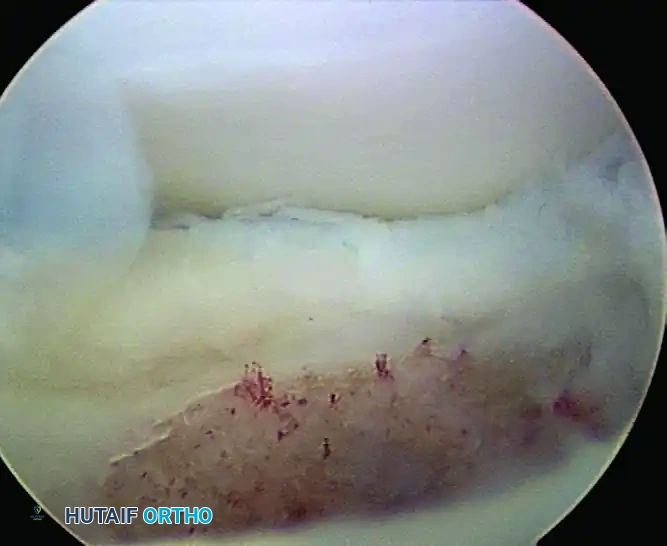

2. Debridement and Microfracture (ICRS Grades 2-4, Contained)

For lesions with fragmented or detached cartilage but a contained crater (intact peripheral rim), microfracture is the workhorse procedure.

- Preparation: The unstable osteochondral fragment is excised using arthroscopic graspers.

- Debridement: An arthroscopic curette and motorized shaver are used to debride the base of the crater down to stable, bleeding subchondral bone. The margins of the lesion must be sharply debrided to create vertical walls, which helps contain the marrow superclot.

- Microfracture: Arthroscopic awls (typically 45-degree and 90-degree angles) are used to penetrate the subchondral bone plate. The holes should be spaced 2 to 3 mm apart and depth should be approximately 3 to 4 mm to access the cancellous marrow.

- Verification: The arthroscopic pump pressure is temporarily lowered to verify the egress of fat droplets and marrow blood from the microfracture holes, confirming adequate depth.

FIGURE 52-67: Microfracture of crater of osteochondritis dissecans lesion less than 1 cm in size with stable lateral rim. Note the punctate bleeding from the subchondral bone indicating adequate marrow stimulation.